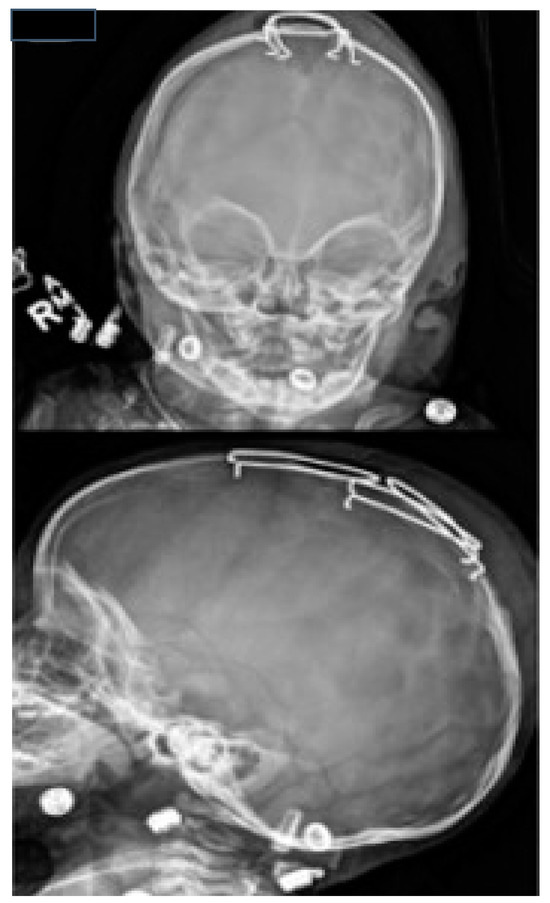

8. Surgical Techniques